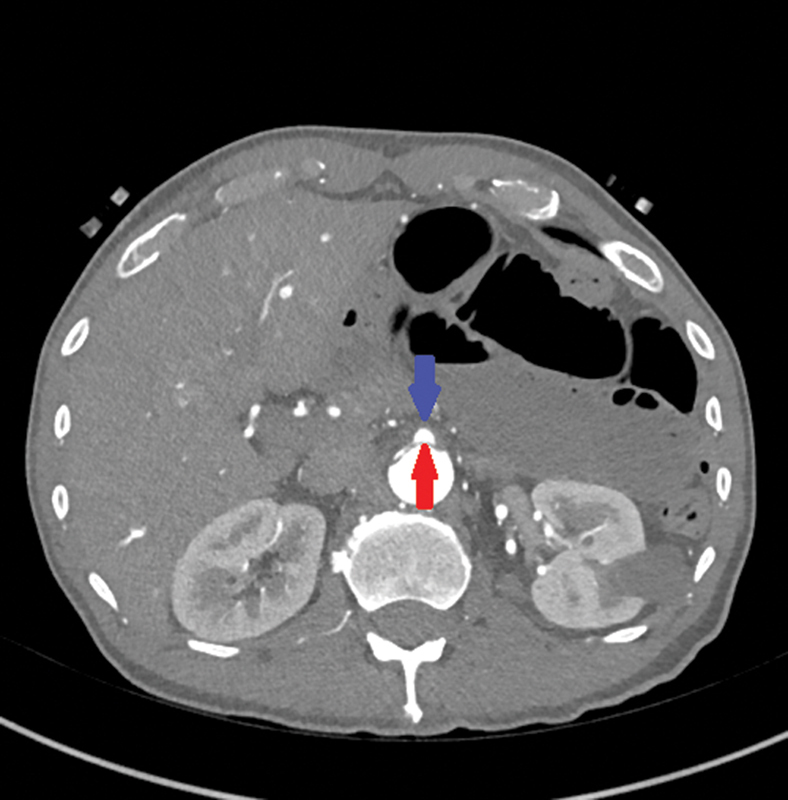

A 57-year-old male patient who underwent an open hemiarch repair with a femoral-femoral crossover bypass and right lower extremity fasciotomies for an acute Type A aortic dissection with limb ischemia presented 5 weeks' postrepair with a 20-pound weight loss due to intermittent hemodynamic collapse of the dissection flap over the origin of the superior mesenteric artery. This case highlights the challenges a dissection flap can cause after an urgent Type A aortic dissection repair.